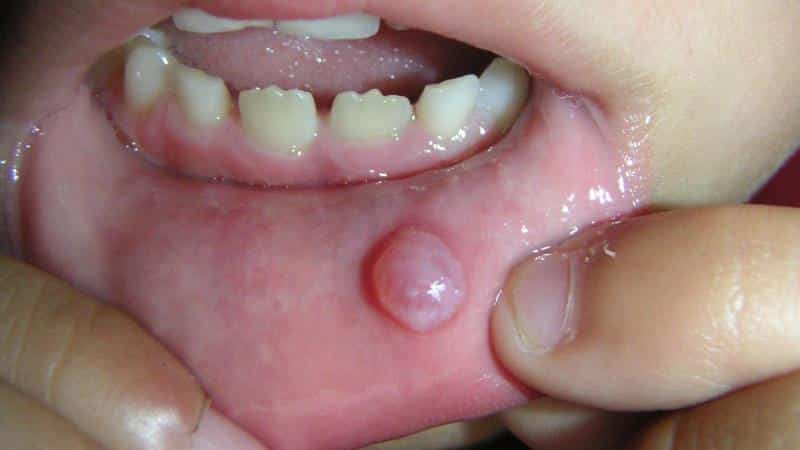

Шишка на внутренней стороне губы, изображенная на фото ниже, может вызывать значительный дискомфорт, затрудняя разговор и прием пищи. В диаметре она иногда достигает двух сантиметров и более. На ощупь это образование ощущается как твердое, а при механическом воздействии, например, во время жевания, из него может выделяться жидкость беловатого или желтоватого оттенка, а также красноватые выделения, если повреждены сосуды.

Шишка внутри губы может иметь не только кистозную природу. При нажатии на нее во время тестирования она углубляется и затем возвращается на место, что также характерно для образований, связанных с железистым эпителием. Подобные опухоли возникают в результате активизации работы эндокринной системы в детском или подростковом возрасте. Большинство шишек могут иметь различные структуры, но проявляются одинаково. Лечение может варьироваться, поэтому важно установить причину их появления.

Когда киста опустошается, она может снова заполняться в своей капсуле, которая служит оболочкой. Это образование подвижно, эластично и окружено небольшим количеством мягких тканей. Боль может возникать при воспалительных процессах. Киста обычно имеет одну камеру, но встречаются и многокамерные формы. Диагностика осуществляется с помощью канального зондирования, что позволяет определить ширину протока и выявить наличие слюнного камня.